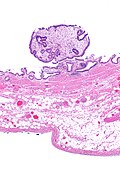

| Caption = Cholesterol polyp of the gallbladder. [[H&E stain]]. | |||

| Micro = foamy macrophages in lamina propria of polypoid lesion | |||

| Gross = polypoid lesion of gallbladder mucosa | |||

Cholesterol polyp of the gallbladder. H&E stain. | |

| LM | foamy macrophages in lamina propria of polypoid lesion |

| Gross | polypoid lesion of gallbladder mucosa |

Cholesterol polyp of the gallbladder is a common benign finding of the gallbladder.

- Benign and common.

- Seen in approximately 6% of removed gallbladders.[1]

- Exophytic lesion of the gallbladder mucosa.

- Foamy macrophages in the lamina propria.